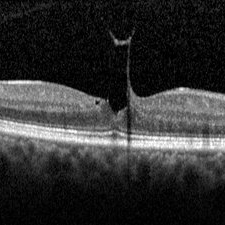

Best Disease Best DiseaseMar 9 2013 by Hamid Ahmadieh, MD OCT of the right eye of a 49-year-old man with decreased VA due to advanced Best disease. Photographer: Soodabeh Fooladin, Negah Eye Center, Tehran Imaging device: Heidelberg Spectralis Condition/keywords: Best disease, optical coherence tomography (OCT)